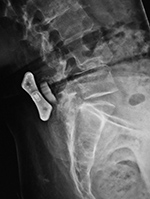

| Pedicle fixation screws and rods |

| 20 year-old woman with L1 vertebral body compression fracture treated with T12-L2 posterior spinal fusion using pedicle screws at T12 and L2 with connecting rods on each side. |